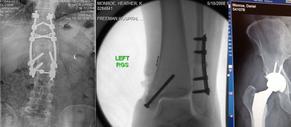

We experienced the death dealing effects inside a violent tornado, but somehow survived despite being critically injured and thrown over 200 yards. The rest of our family however accounted for a significant percentage of the fatalities that occurred that day. This was federally declared disaster #1760.